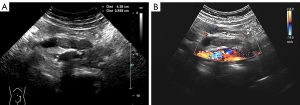

A urologic ultrasound examination revealed dilation in the upper left ureter, characterized by an internal diameter of approximately 1.60 cm. Additionally, a hypoechoic mass measuring 3.92 cm × 1.47 cm was observed 5.0 cm from the left renal hilum-ureteral junction (within the ureter), displaying a class I blood flow signal on color Doppler flow imaging (CDFI). Adjacent to the left renal hilum, an enlarged hypoechoic lymph node measuring about 2.33 cm in diameter was identified (Figure 1). Computed tomography urography (CTU) revealed a soft tissue density mass within the lumen of the left mid-ureter, appearing as a strip measuring approximately 1.20 cm at its widest point, with a measured area of involvement of about 4.10 cm. The CT attenuation values were 42 Hounsfield units (HU) in the plain phase, 73 HU in the corticomedullary phase, and 70 HU in the nephrographic phase, with enhancement scans displaying moderate enhancement. Both the ureter and the renal calyces above the lesion exhibited dilation and hydronephrosis, contributing to a reduction in both volume and perfusion of the left kidney. Adjacent to the abdominal aorta and left iliac vessels, multiple enlarged lymph nodes were evident (Figure 2).